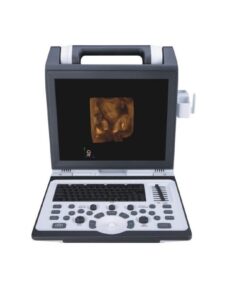

Optional |

Real photos

Related products